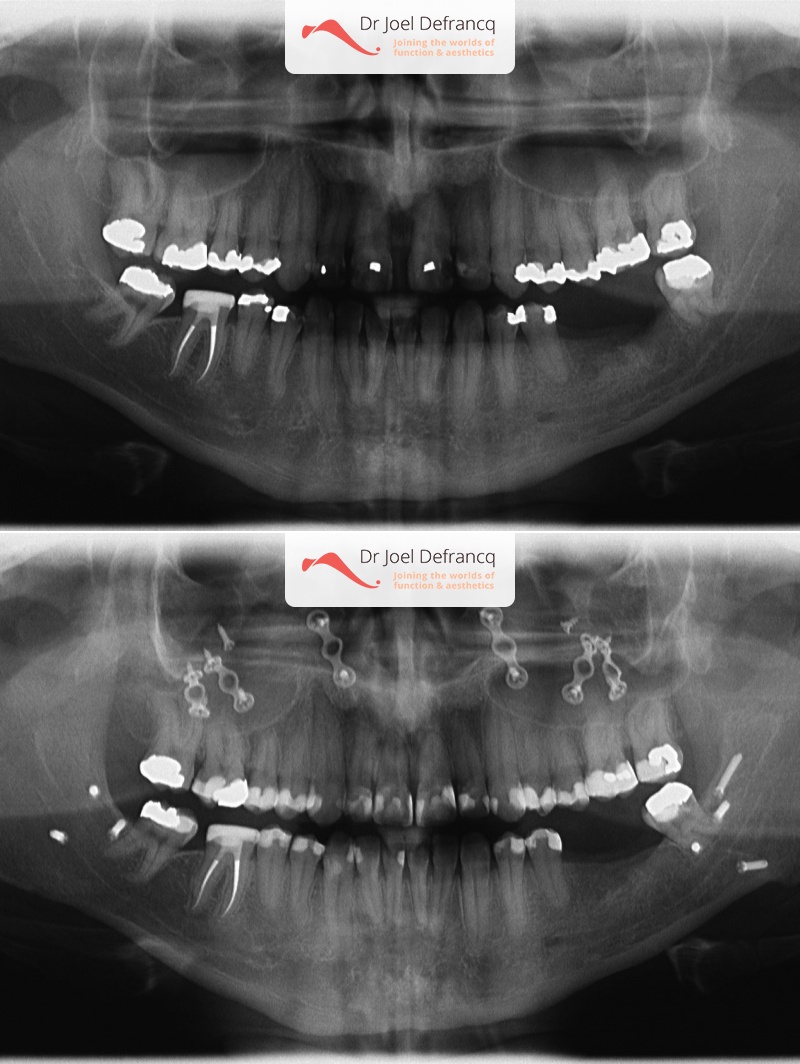

Rudy: upper jaw too far back

Dentale diagnose

- Klasse III

Kaakchirurgie

- Verlenging bovenkaak (Le Fort I)

- Onderkaak rotatie

- Kinchirurgie